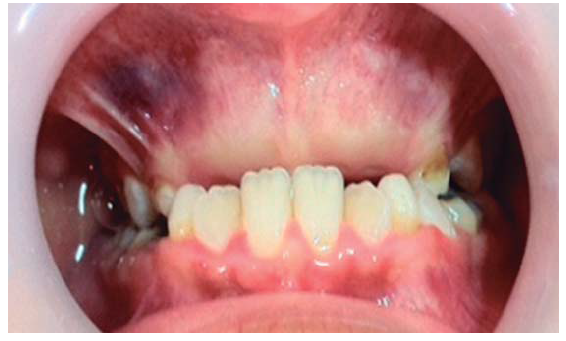

In order to assess the patient, panoramic X-rays were taken as well as an imaging study by means of computerized axial tomography. Intraoral examination revealed healthy mucosae and expansion of the cortical bone in the anterior section of the upper jaw, ankylosis, presence of palatal tori and mandibular bilateral tori (Figure 1). General physical examination revealed bilateral bone excrescences in the upper section of the shoulder blades. At a later date a colonoscopy was conducted in order to assess presence of intestinal polyps as well as association to Gardner's syndrome (which proved to be negative).